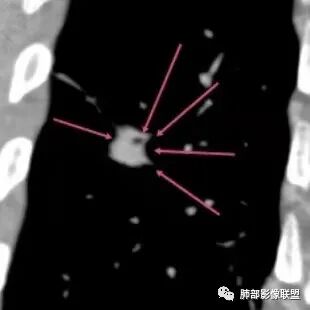

男58岁,肺部偶发结节,临床嗜睡,脑血管病变缺氧?还是感染肿瘤继发,安全起见脑部磁共振做一个。   肺结节影像特征:1 长毛刺 2 尖角征 3 长条索移行  4 轻度支扩 5 血管从尖角进入,6 总体条片状病灶,恶性证据不多,炎性病灶,抗炎两周,一月复查。

右肺下叶条片状稍高密度影,边缘收缩为主,尖角征 、U型凹陷征,周围长软毛刺征,支气管通畅,临近胸膜牵拉,考虑炎性病灶,鉴别腺癌。

1.病例特点:中老年男性,长期睡眠异常(嗜睡),焦虑状态。病例右肺下叶长条片状病灶,实性密度为主,轻度强化,边缘多平直(可见尖角征),未见明显膨隆分叶及毛刺,边缘见模糊磨玻璃影,未见钙化、液化或空洞。病灶长轴顺延下叶支气管方向,长索条状牵张于胸壁肺门间,轻度胸膜凹陷。病灶内见支气管、血管通行,气管略壁厚。

2.综合分析:条片状病灶,边缘平直,尖角,未见典型的分叶毛刺,少张力,也未见边界清楚的磨玻璃晕,同侧肺门及纵隔未见增大淋巴结等等,总之,如多数老师分析,缺乏典型恶性肿瘤影像学特征。